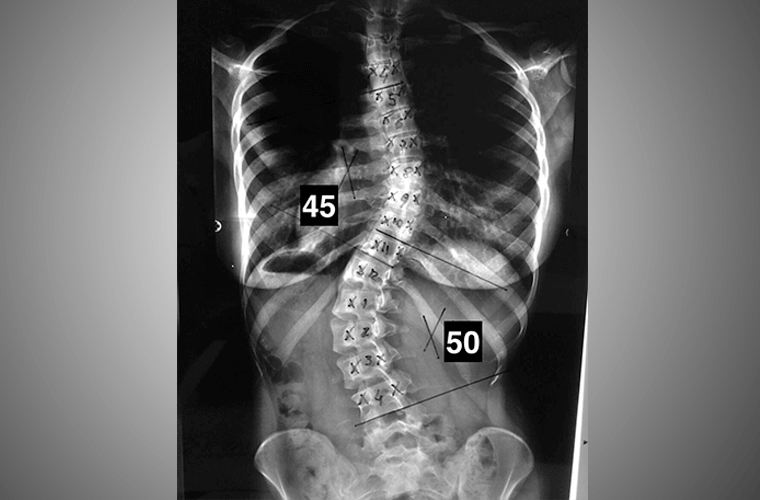

Entre os dias 2 e 5 de dezembro, o Hospital das Clínicas da Faculdade de Medicina de Botucatu – Unesp (HCFMB) será palco de um mutirão de escoliose. Problema de saúde comum, a escoliose pode ser caracterizada por um encurtamento da coluna causado por uma curvatura lateral.